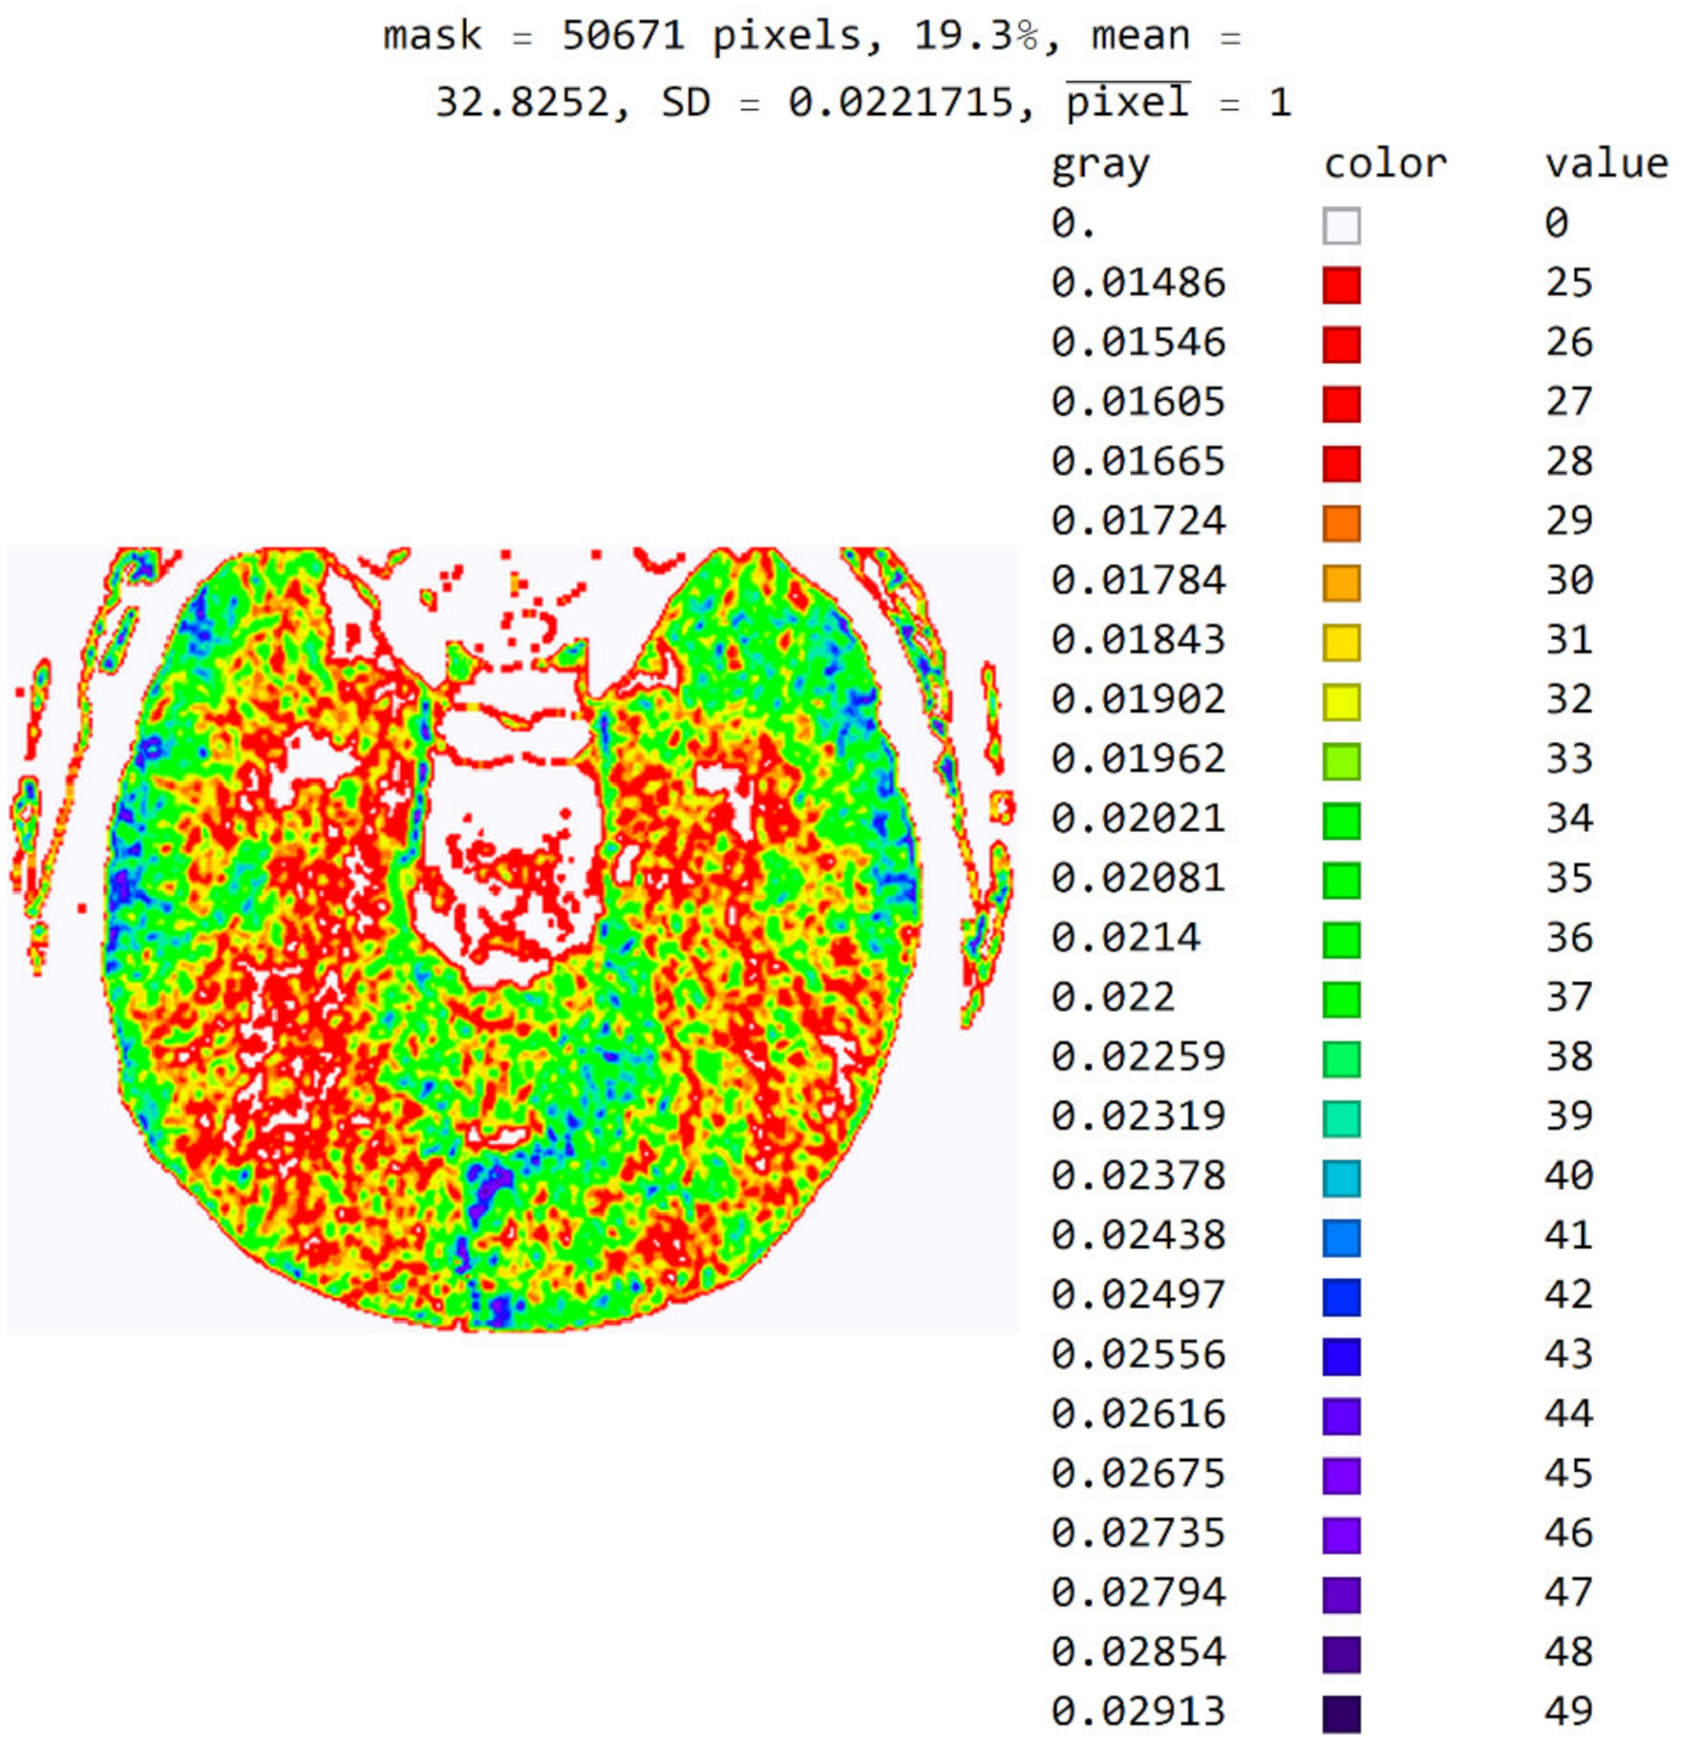

2.2. Smart Visualization Method (SVMI)

3.1. Technological Description